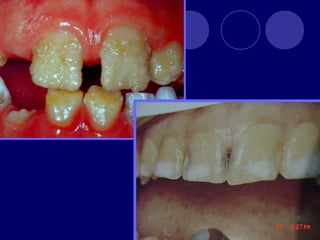

AMELOGENESIS IMPERFECTA  Hipoplásico: Zonas ausentes de esmalte  Afecta más a caras vestibulares  Esmalte: blanco amarillento y marrón claro, consistencia dura, fosas y surcos oscuras, delgado  Hipocalcificado:  Cualitativo  Esmalte frágil, fácil de desprender  Rx: falta de contacto entre dentina, esmalte  Hipomaduro:  Disminución en el contenido mineral  Esmalte blando y rugoso, veteado de blanco a marrón (esmalte en copos de nieve)  Más frecuente en caras vestibulares y dientes superiores

ANOMALÍAS DE ESTRUCTURA AMELOGENESIS IMPERFECTA: (Hipoplásico, hipocalcificado Hipomaduro)  DISPLASIA AMBIENTAL DEL ESMALTE